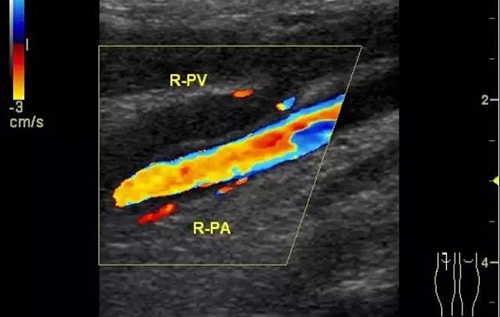

下肢深靜脈血栓形成后綜合征的診斷主要依靠靜脈造影和彩色超聲多普勒,而彩超機具有無創、重復性好、準確率高的優點,逐漸成為診斷此病的首選。

彩色普勒超聲診斷儀,線陣探頭,頻率7.5~10MHz。受檢查者先取仰臥位,患肢髖關節略外旋,大腿輕度外展且膝關節略曲,使整個下肢呈松弛狀態。自上而下順序檢查髂外、股總、股淺、股深及大隱靜脈;之后取俯臥位,檢查靜脈及小腿靜脈。以縱切和橫切顯示血管,灰階超聲主要觀察血管內徑、管壁結構及血栓情況,CDFI主要觀察管腔內有無血流顯示、充盈缺損及血液返流情況,必要時擠壓小腿腓腸肌以利血流顯示。

彩色多普勒超聲具有很高的特異性和敏感性,是超聲診斷技術的重要發展。

彩超診斷下肢深靜脈血栓形成后綜合征具有無創、實時、動態、重復性好、準確率高的特點,且能充分了解血管內外的解剖學改變,觀察靜脈管壁、血流充盈、靜脈瓣返流程度以及側支循環是否建立和血栓的溶液情況,可直觀地觀察到血流動力學改變,所以具有很高的使用價值。通過對治療前后聲像圖的對比,可以提示臨床的治療效果,對于臨床治療具有很大的指導作用。